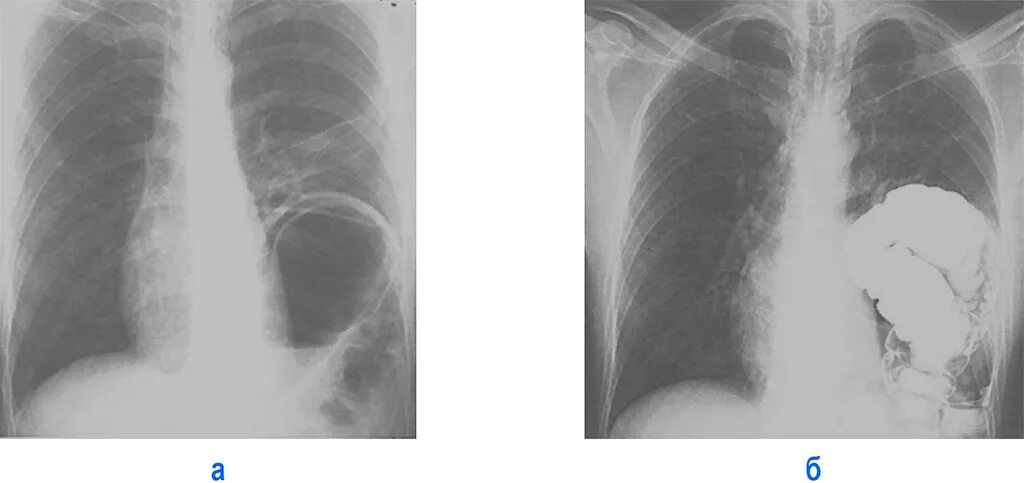

Ущемление грыжи диафрагмы